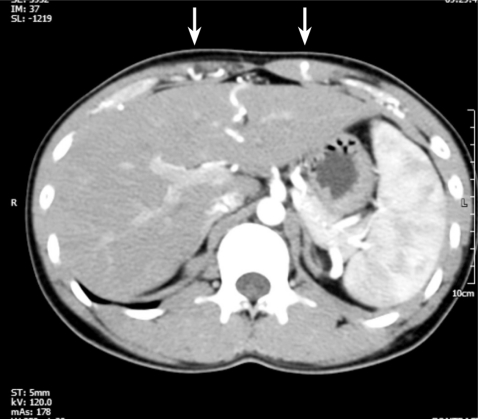

A 21-year-old male with secondary hypertension was referred to our facility by a general physician. The patient had no family history or risk factors for hypertension. During the physical examination the patient's blood pressure (BP) measured 190/110 in both arms and no cardiac murmur or bruit was detected. Renal Doppler sonography was performed to identify the potential cause of secondary hypertension, specifically renal artery stenosis. Tardus-parvus pulse waves were noted in both renal intra-arteries (Fig. 1A and 1B); however, a subsequent abdominal computed tomography (CT) did not show any evidence of renal artery stenosis and both adrenal glands looked normal. There was a noted tortuous and engorged superior-epigastric artery along the abdominal wall (Fig. 2).

Figure 1

(A) Right renal doppler sono shows tardus-parvus wave pattern. Notice decreased arterial peak velocity and delayed acceleration time which indicates stenosis of proximal artery. (B) Left renal doppler sono shows tardus-parvus wave pattern which is similar to right renal doppler finding.